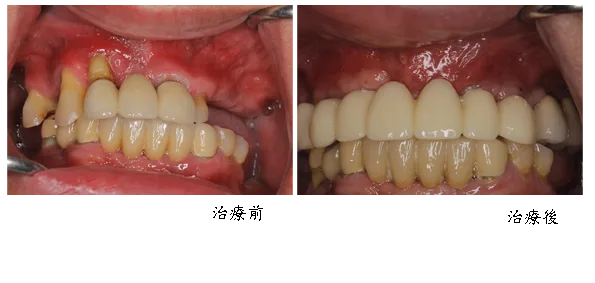

[ 邱小姐植牙案例 ]